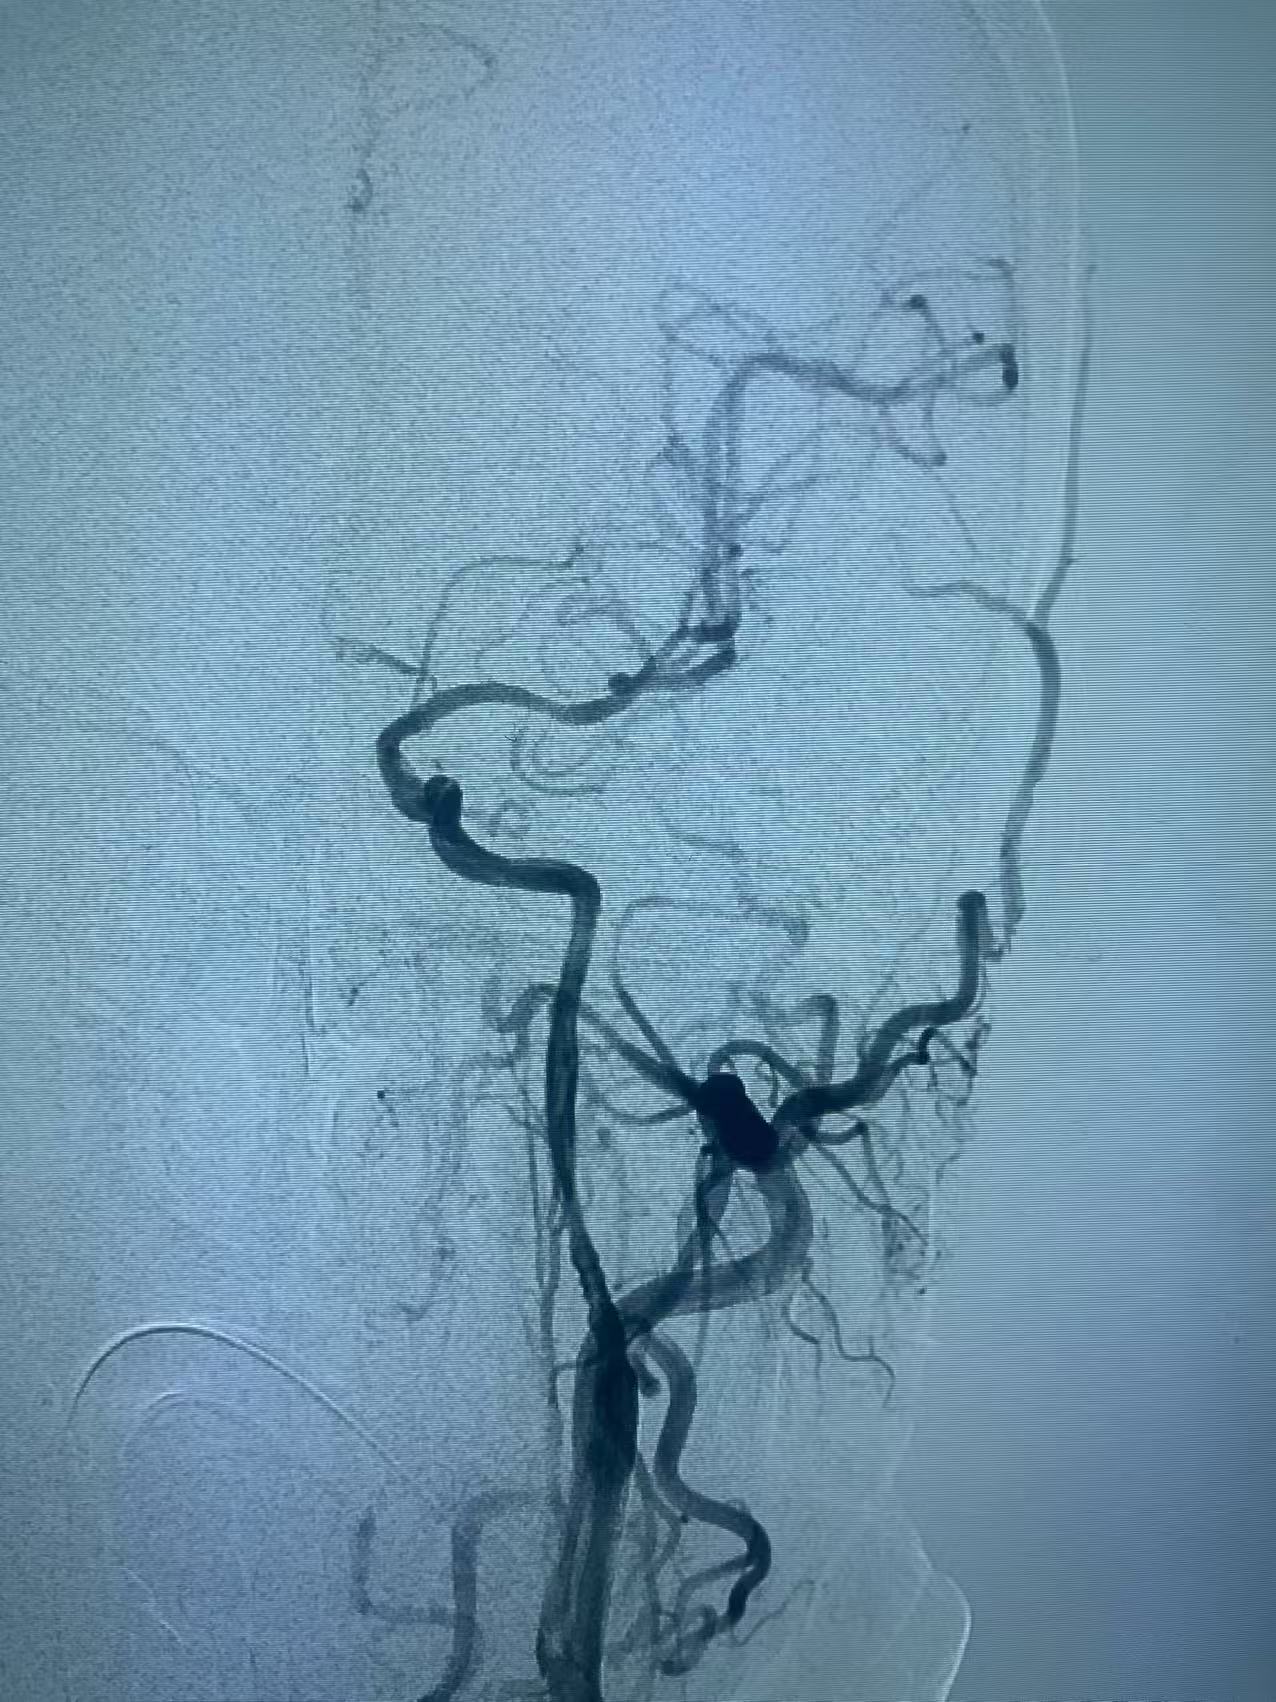

颈内动脉开口重度狭窄基础之上的急性闭塞